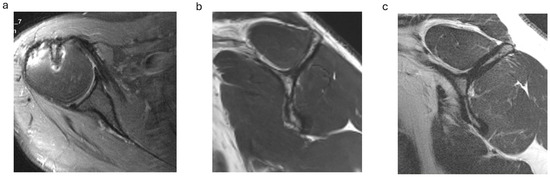

On postoperative MRI scans, subscapularis tendon repair integrity was graded on axial T2-weighted images using the Sugaya classification, with types 1, 2 and 3 graded as intact tendons (Figure 1a) and types 4 and 5 with tendon discontinuity graded as a retear [20,21]. Subscapularis muscle atrophy was evaluated on the Y-shaped view in the sagittal plane: no atrophy (grade 0), mild atrophy (grade 1), moderate atrophy (grade 2) and advanced atrophy (grade 3) (Figure 1b,c). The MRI scans were graded separately by two investigators (CB and SP) and in consensus in case of discrepancy.

Subscapularis muscle atrophy grading on the sagittal MRI scans in the ARG group showed no or mild atrophy (grade 0 or 1) in 13 cases (72%) and moderate atrophy (grade 2) in 5 cases. In the ORG, no or mild atrophy was present in 11 cases (69%) and moderate atrophy in 5 cases (Figure 1b,c; Table 3).

Figure 1. (ac). Postoperative subscapularis imaging. (a) Intact subscapularis tendon in the axial plane (Sugaya type 1). (b) Subscapularis muscle with no atrophy (y-shaped plane). (c) Advanced subscapularis atrophy of the upper muscle portion.